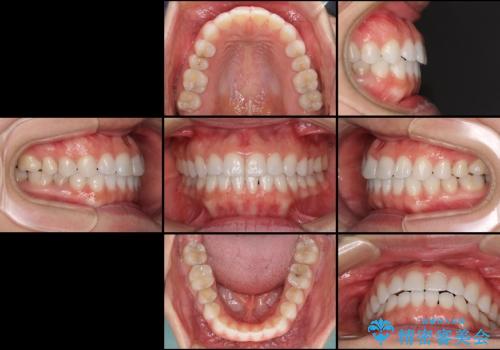

- 上下の前歯の反対咬合を気にして来院された患者様です。

インビザラインを用い、下顎はIPR(歯と歯の間を削る)と歯列全体を後方に移動させ、上顎は前歯を持ち上げることで、反対咬合を改善していくこととしました。

インビザラインによる反対咬合の改善は、上の歯が下の歯を乗り越えていく期間に咬み合わせが非常に不安定となり、治療が長期化することがあります。

こちらの患者様も、一時的に前歯でしか咬めない時期がありましたが、比較的早く咬み合わせが安定し、1年ほどで治療を終えることができました。